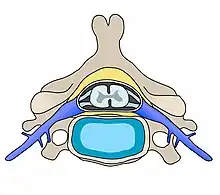

D'après le Journal of Manipulative and Physio Therapy[1], les manipulations vertébrales auraient un effet significatif sur la neurologie du corps humain, et ce par le biais des nerfs rachidiens et les dysfonctionnements neurologiques inhérents à une perturbation mécanique d'une articulation entre deux vertèbres, appelée subluxation vertébrale. La subluxation vertébrale est susceptible de survenir entre n'importe quels segments jointifs de la colonne vertébrale, du coccyx aux hautes cervicales, affectant alors la « libre circulation de l'influx nerveux » au niveau du trou de conjugaison inter-vertébral.

Physiologiquement et biomécaniquement parlant, une fixation entre deux segments vertébraux ou un déplacement de l'un des deux en rapport à l'autre est associée à :

- une kinésiopathologie vertébrale[2], c'est-à-dire une diminution des amplitudes de mouvement entre deux segments vertébraux adjacents, ou une aberration de la mobilité de ces deux vertèbres ; une mobilité non fluide et saccadée à ce niveau lors de la flexion axiale du rachis par exemple ;

- une neuropathophysiologie, soit un état non optimal voire pathologique des fonctions neurologiques associées à l'articulation en état de subluxation, les nerfs se trouvant comprimés à hauteur du trou de conjugaison ;

- une myopathologie, c'est-à-dire une aberration des tonicités musculaires (hypo ou hyper-tonicité des muscles) adjacentes aux segments vertébraux en question, les muscles profonds par exemple, notamment les muscles transversaires épineux ;

- une physiopathologie, les tissus tels que les ligaments, tendons et tissus conjonctifs qui environnent la zone de subluxation vont se trouver modifiés physiologiquement, avec notamment :

- des œdèmes sur les ligaments et/ou tendons immédiatement adjacents ;

- une inflammation de ces derniers ;

- un tissu scareux, type cicatrice qui va s'installer dans le trou de conjugaison après une certaine période d'inflammation, impactant alors le bon déroulement neurologique des nerfs qui émanent de la zone ;

- une pathophysiologie, c'est-à-dire les conséquences pour l'organisme de la subluxation, qui seront de deux ordres :

- directs : lorsque le mouvement articulaire se trouve modifié à long terme, la qualité histologique de l'articulation peut s'en trouver affectée, avec des conséquences telles que l'arthrose, des ostéophytes, discopathies[3], etc.

- indirects : les fonctions neurologiques étant dès lors modifiées ou diminuées, toute structure de l'organisme irriguée par ce nerf en aval de la zone subluxée serait dès lors affectée. De ce fait, à long terme, un muscle par exemple pourrait s'atrophier à cause d'un influx nerveux aberrant venant l'irriguer.

Dans son étude comparative parue en 2000[11], Scott Haldemann observe, peu de temps après la manipulation d'un segment vertébral, une modification de la qualité et de la quantité des influx nerveux provenant du système nerveux central (efférent) et allant vers celui-ci (afférent). Une sorte de normalisation de ces influx semble se restaurer. Ceci s'explique par la simple compression, directe (articulation contre nerf) ou indirecte (muscles adjacents hypertoniques contre nerf) ayant subi un changement mécanique rapide. Une fois décomprimé, le tissu nerveux est à nouveau pleinement fonctionnel, la configuration des tissus adjacents au nerf ayant été modifiée. On parle principalement ici de la zone d'émanation du nerf entre les vertèbres, nommée foramen intervertébral.